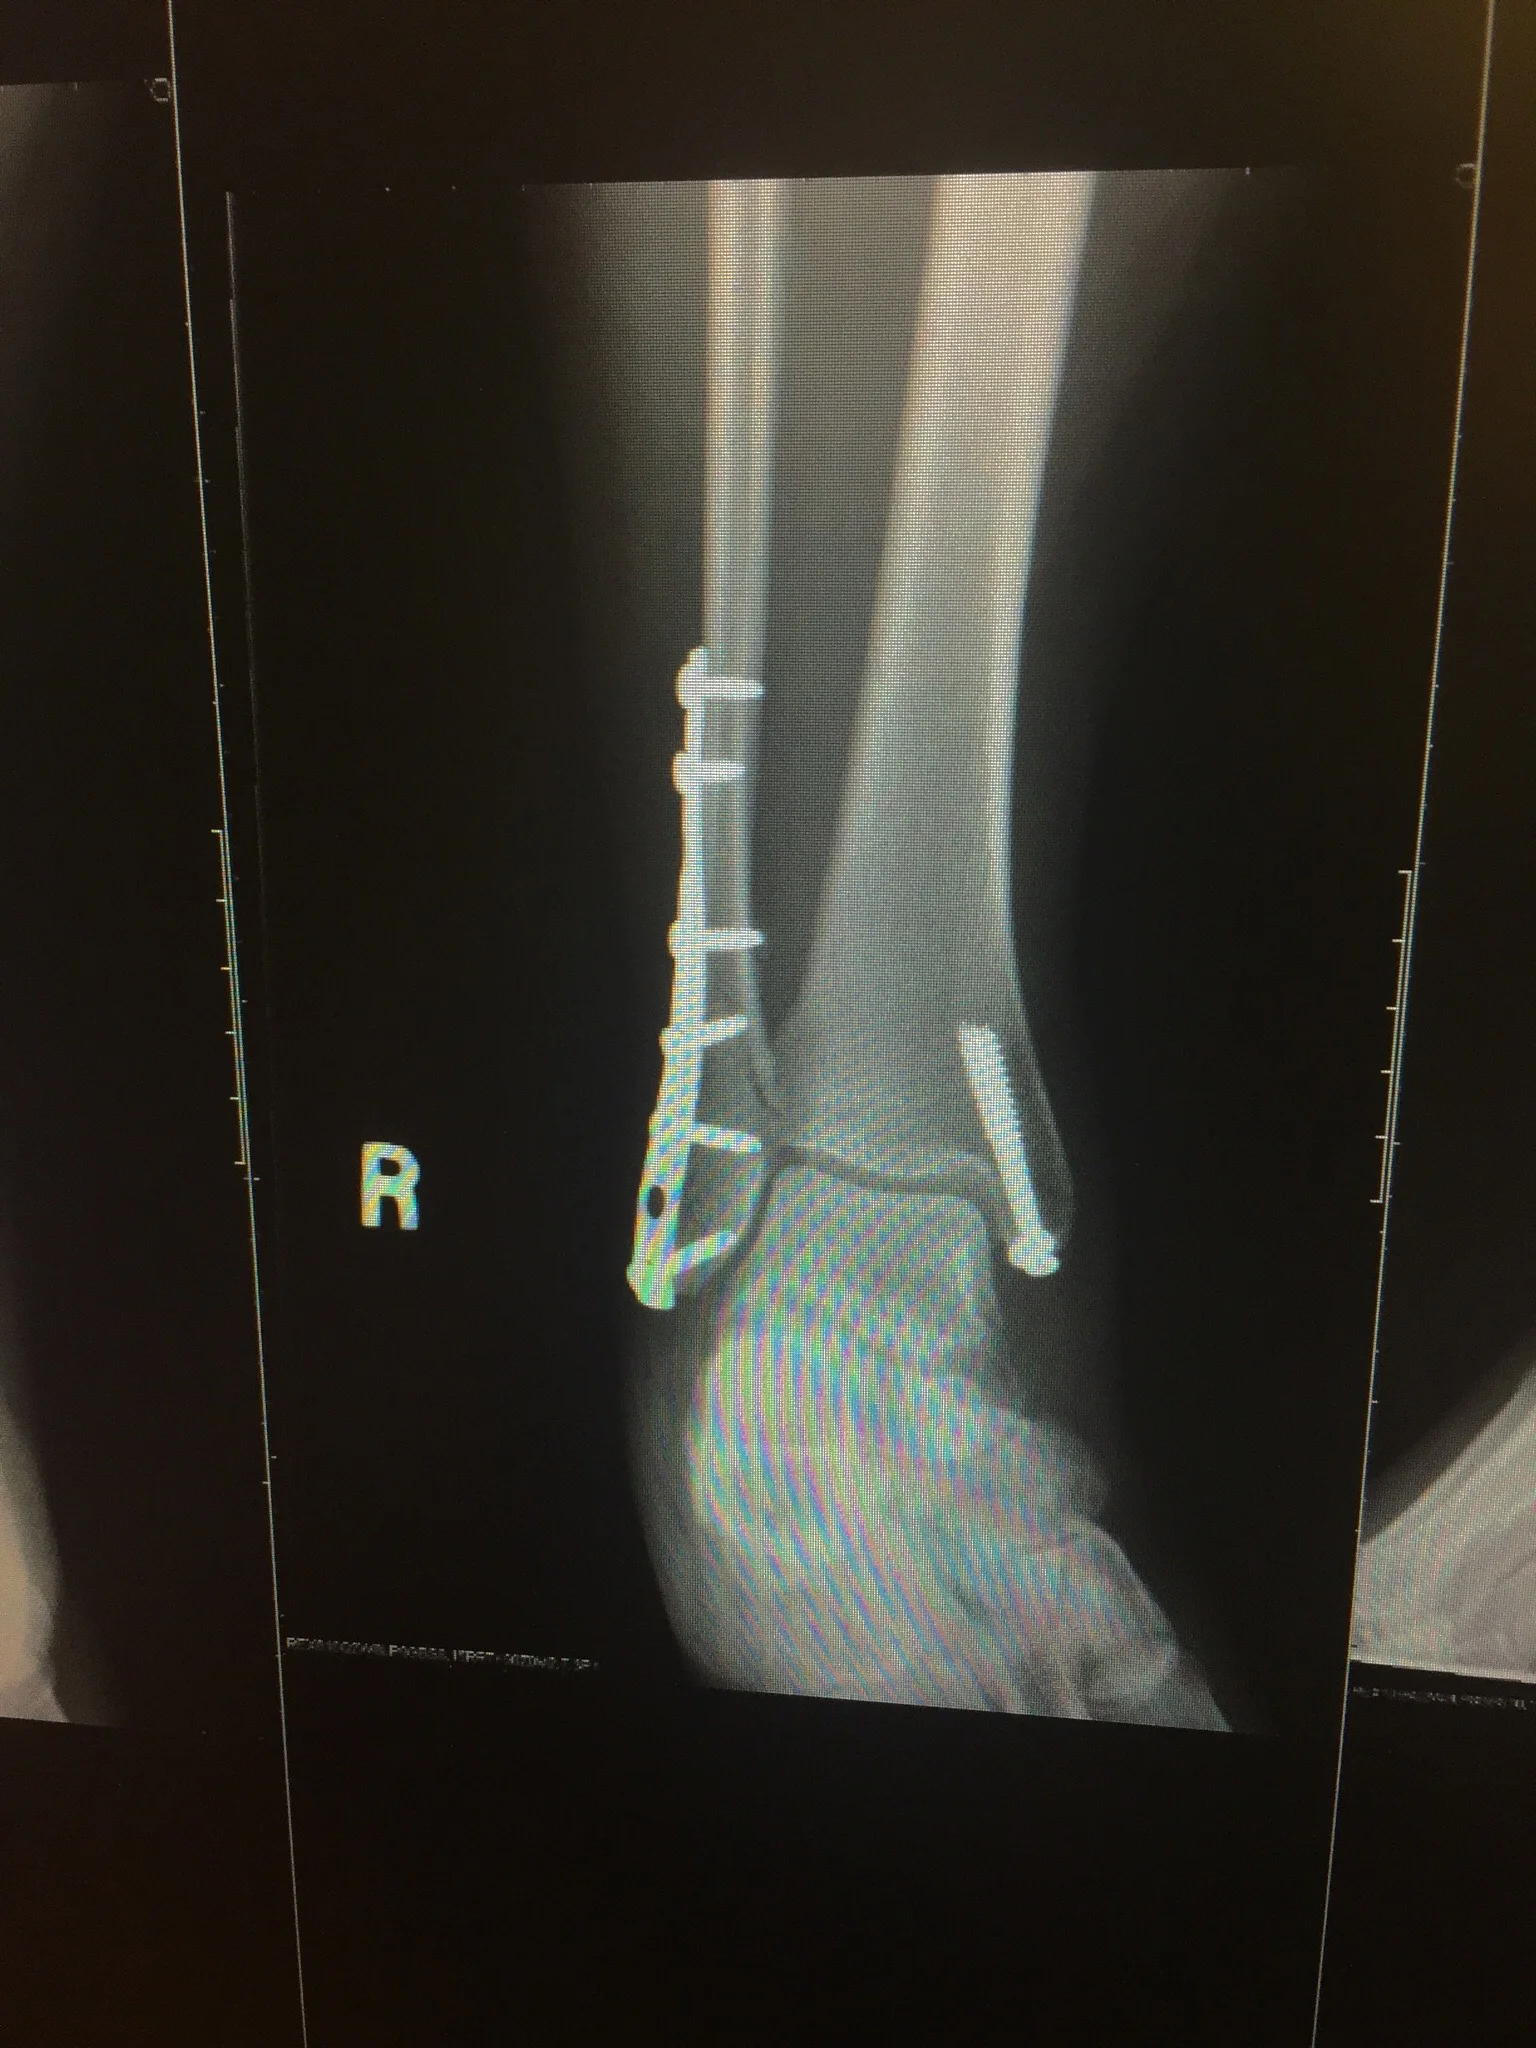

I have a plate and 8 pins down my fibula and one longer screw further down. Removal of Tibial Plate and Screws.

Posted 6 years ago 31 users are following. I had a fall on Friday 13th Feb and surgery followed. I have a plate and 8 pins down my fibula and one longer screw further down.

The plate and screws are destined to stay in place but there seems to be conflicting information on the longer screw. A small screw or wire may require little or no limitation of activity. High stress activities such as marathon training and jumping might be restricted for a period of time.